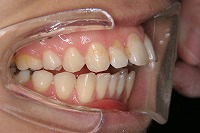

23歳5か月

上の前歯が出ている事を主訴に来院された、23歳2か月の女性です。診断「下顎骨の後方回転による骨格性上顎前突で開咬を伴う」上顎は両側第1小臼歯、下顎は抜歯をせず治療を行いました。